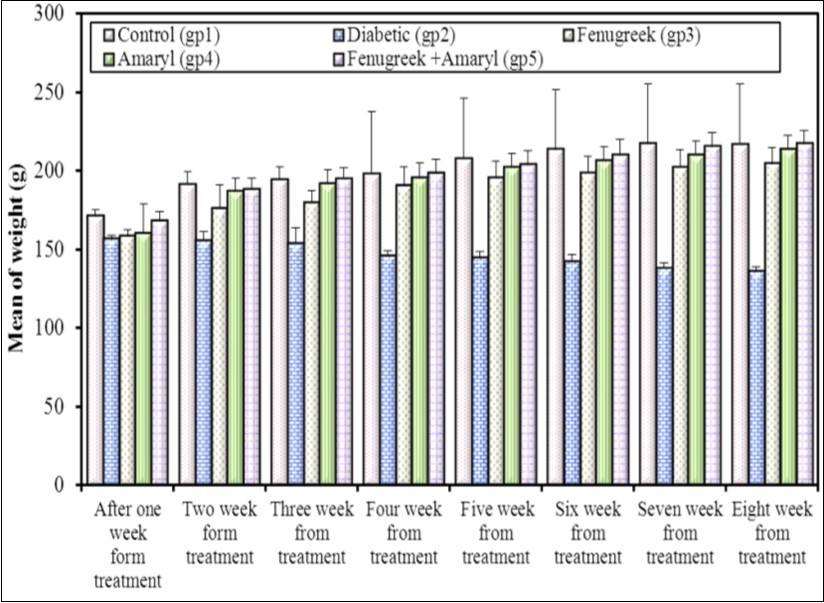

Body Weight Through Eight Weeks of Treatment

Results showed a reduction in the body weight in STZ injected rats. This reduction may be attributed to insulin depletion provoking a loss of adipose tissues and the changes in carbohydrates and protein metabolism that occur in rats with Streptozotocin-induced diabetes 6. The increase in the body weight of group (5) exceeds that of group (3) and group (4). It reached the same value of the control group at the eighth week. The body weight of group (3) and group (4) improved during the experiment (Figure 1). Fenugreek aqueous extract significantly increase the body weight. It exhibited antioxidant property which protects the functional organs and increase the body weight 7. Glimepiride increases the body weight significantly 8. Combination of Fenugreek and Glimepiride showed more increase in the body weight compared to other groups.

Figure 1.Effect of Fenugreek and Glimepiride on the body weight of diabetic male albino rats.